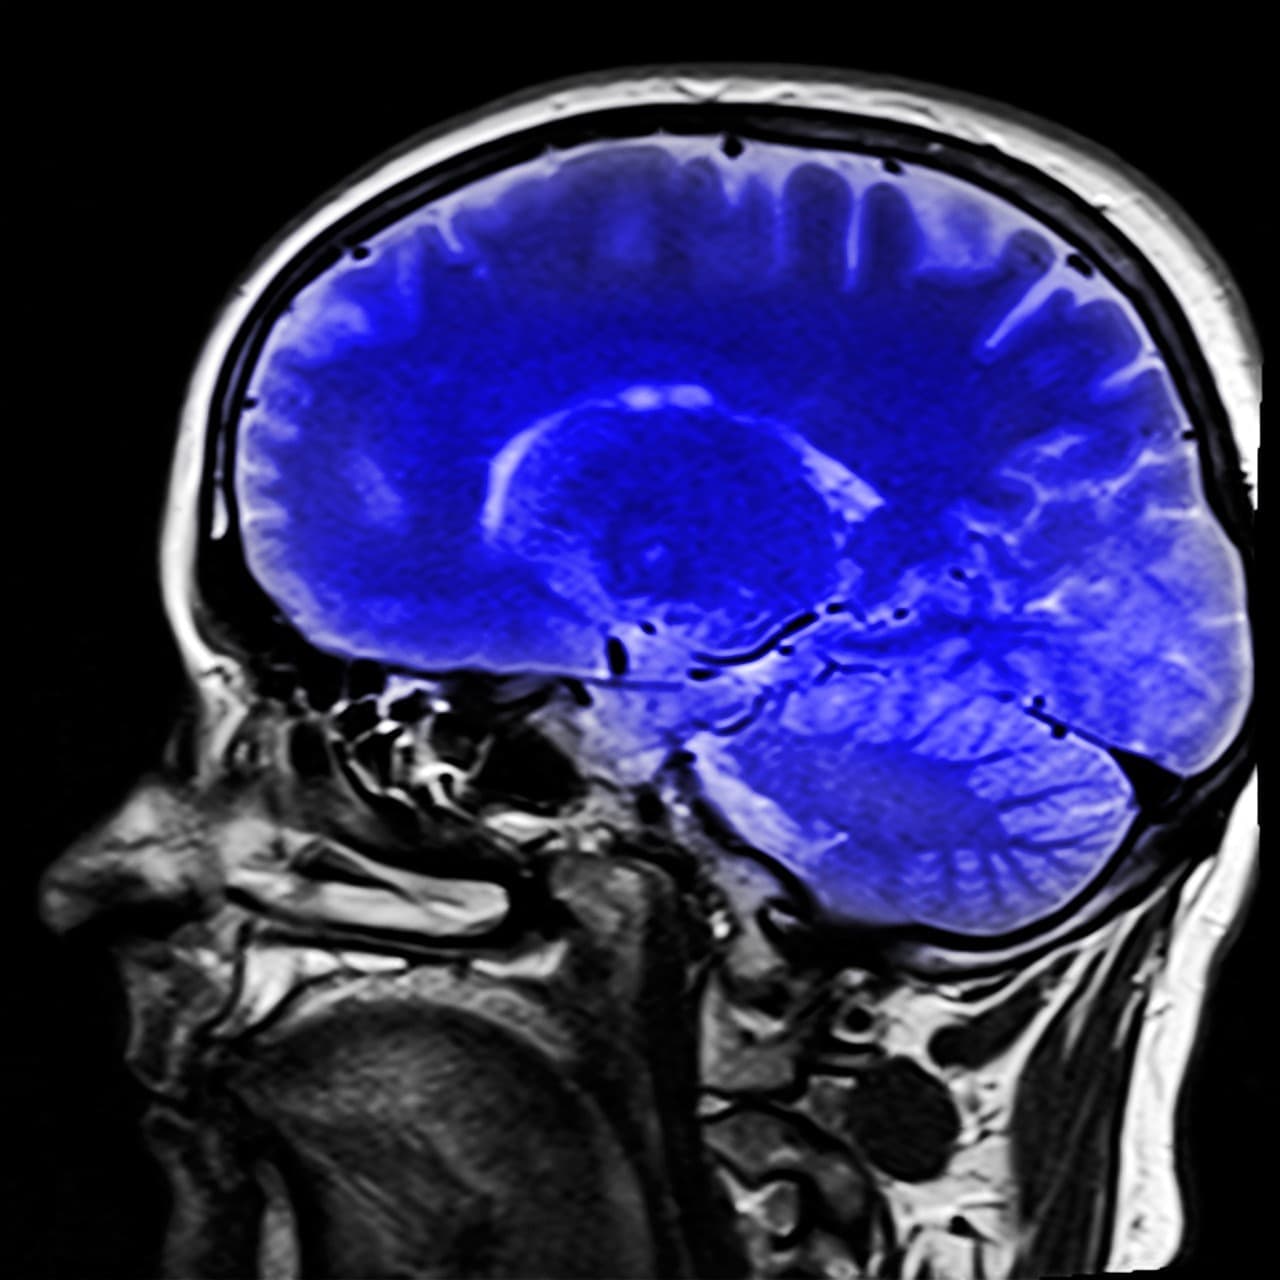

Meta repousse les limites de la communication grâce à Brain2Qwerty, une interface cerveau-ordinateur non invasive qui pourrait transformer notre manière d'interagir avec le numérique. Ce projet ambitieux, présenté pour la première fois en 2017, a connu d’importantes avancées expérimentales et soulève à la fois de grands espoirs et des interrogations éthiques.

Meta a dévoilé dès ses débuts l’idée d’un casque capable de convertir nos pensées en texte avec une rapidité impressionnante – 100 mots par minute – destiné en priorité aux personnes paralysées. Les recherches menées, en collaboration avec le Centre basque sur la cognition à Saint-Sébastien, ont impliqué 35 volontaires dont les signaux cérébraux ont été enregistrés lors d’activités de frappe sur un clavier. Grâce à la magnétoencéphalographie, une technique qui capte les champs magnétiques produits par l’activité neuronale, l’intelligence artificielle a pu identifier des motifs récurrents et transformer ces signaux en texte avec un taux de précision avoisinant 68 %. Bien que le dispositif initial présente des obstacles pratiques – avec un poids avoisinant la demi-tonne et un coût de 2 millions de dollars – ces résultats réduisent considérablement l’écart entre les méthodes invasives comme Neuralink et non invasives, ouvrant la voie à des applications médicales et commerciales innovantes.

En parallèle, d’autres chercheurs ont exploré des variantes du projet Brain2Qwerty pour décoder l’activité cérébrale avec une haute résolution temporelle, atteignant parfois des taux d’erreur de seulement 19 %. Cette recherche met en lumière non seulement le potentiel de la lecture automatique des pensées dans le domaine des neuroprothèses, mais également sa capacité à servir d’outil de recherche cognitive. Les résultats obtenus offrent un aperçu inédit des mécanismes cérébraux liés à la production du langage, facilitant des applications futures dans la réalité virtuelle, la communication assistée et même dans l’évaluation de l’impact publicitaire.